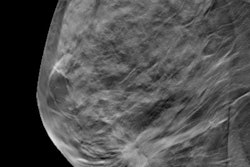

Women who adhere to early and regular screening mammography have lower mortality rates and benefit more from breast cancer therapies at the time of diagnosis of the disease, according to a study published online November 8 in the journal Cancer.

The breast cancer mortality rate among women who undergo screening is 60% lower 10 years after diagnosis than in women who do not receive screening, wrote a group of investigators led by Dr. László Tabár, professor emeritus of radiology and former medical director of the mammography department at Falun Central Hospital in Sweden.

In addition, the incidence of fatal breast cancers within 10 years of diagnosis per 100,000 women ages 40 to 69 during the screening period was 60% lower in those who participated in screening than in those who did not. For cancers that were fatal within 20 years of diagnosis, the breast cancer mortality rate was 47% lower in women who underwent screening than in those who did not.